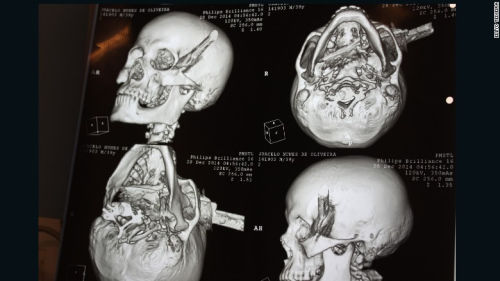

男子被人用刀刺中頭部,直穿頭骨。

中新網(wǎng)1月4日電 據(jù)外媒報(bào)道,巴西一名男子在與他人爭吵過程中被人用刀刺中頭部,直穿頭骨。在經(jīng)過2個(gè)半小時(shí)的手術(shù)后,該男子奇跡存活。

據(jù)報(bào)道,39歲受害男子系一名出租車司機(jī),事發(fā)時(shí)他正在一個(gè)酒吧喝酒,結(jié)果與人發(fā)生口角。男子被刺中4刀,其中3刀刺中身體,1刀被插進(jìn)頭部,橫穿過左眉骨。

醫(yī)生說,刀已經(jīng)完全穿過了男子的頭部,幾乎就要接近嗅覺神經(jīng),但僅僅破壞了部分味覺神經(jīng)。男子幾乎就要失去視覺、嗅覺和味覺,但是沒想到,幸運(yùn)的是他將毫發(fā)無損。